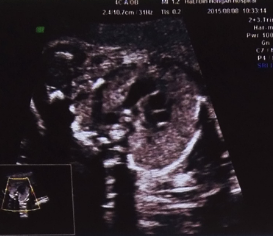

今天做四维,大夫不太确定胎儿心脏主肺动脉是否正常的,有点担心,让过一个月再去,有能看懂这个四维图的

今天做四维,大夫不太确定胎儿心脏主肺动脉是否正常的,有点担心,让过一个月再去,有能看懂这个四维图的吗?

这个图也只实裕有b超医生能看明白,既然不确定就别多想,听医生的过一个月再去检查就可以了,现在洞做要做的锈铜暖就是放宽心情,对胎儿有好处